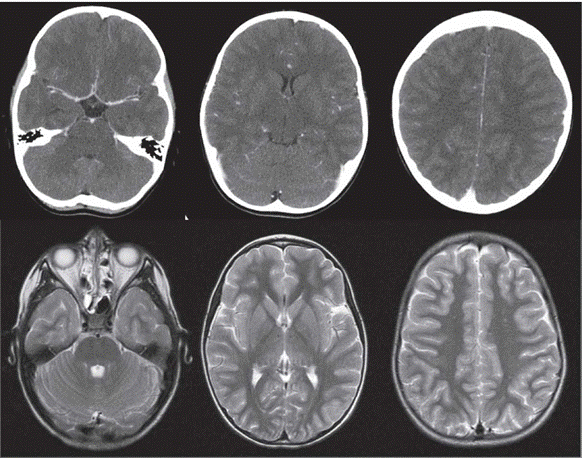

En resonancia magnética cerebral al sexto 6 día de enfermedad, presenta edema cortical mínimo bifronto-parietal (figura 2). Al día doceavo 12 de enfermedad, la resonancia magnética cerebral evidencia realce cortical mínimo bifrontoparietal mediales y temporales, así como compromiso de tallo en región anterior izquierda y leve compromiso de bulbo bilateral a nivel lateral con realce de la señal de pares craneanos simétricos (III, V, VI, VII, VIII y complejo de pares bajos). Se confirma imagenológicamente romboencefalitis mas encefalitis (figura 3). Se identifican bandas oligoclonales positivas, 3 bandas en líquido cefalorraquídeo (LCR), no presentes en sangre. Anticuerpos IgG anti-GQ1b positivos, 1 en 6 400 (VR 1 en 100); anticuerpos antireceptor NMDA negativos (tabla 1). Electroencefalograma 1-2 normal y electromiografía y velocidades de conducción ondas H ausentes. Ondas F discretas. Presencia de polineuropatía desmielinizante aguda. Potenciales auditivos de tallo cerebral con enlentecimiento. Potenciales somato-sensoriales normales.

Resonancia cerebral del sexto día de enfermedad del paciente.

Figura 2: Resonancia cerebral del sexto día de enfermedad del paciente.

Nota: arriba, cortes axiales de RM cerebral, secuencias FLAIR, que muestran áreas de edema cerebral cortical frontoparietal, temporal y occipital bilateral (flechas). Abajo, cortes axiales con información de difusión DWI y secuencia de susceptibilidad magnética, sin evidencia de infarto o sangrado agudo y coronal T2, nuevamente áreas de edema cerebral en corte coronal (flechas). Fuente: autores.